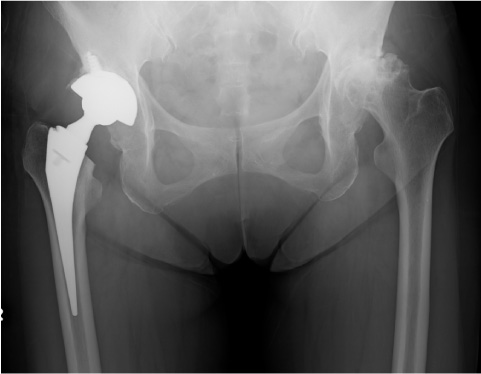

股関節のいたんでいる部分を取りのぞき、人工の関節に置きかえる手術です。人工関節は、基本的には金属と、金属に対して滑りのいいプラスチックから作られています。人工股関節は、金属製の大腿骨(だいたいこつ)の中に入れる棒状のステムというものとボール、そして骨盤側のカップと、その中に入るプラスチックが組み合わさって構成されます。

実際の人工股関節の手術では、関節の痛んだ部分を取り除いて、骨盤側には金属製のカップをボルトで固定し、大腿骨側には、金属製のステムを挿入します。そして、その先端のボールとプラスチックが組み合わさってスムーズに動く人工関節となるわけです。